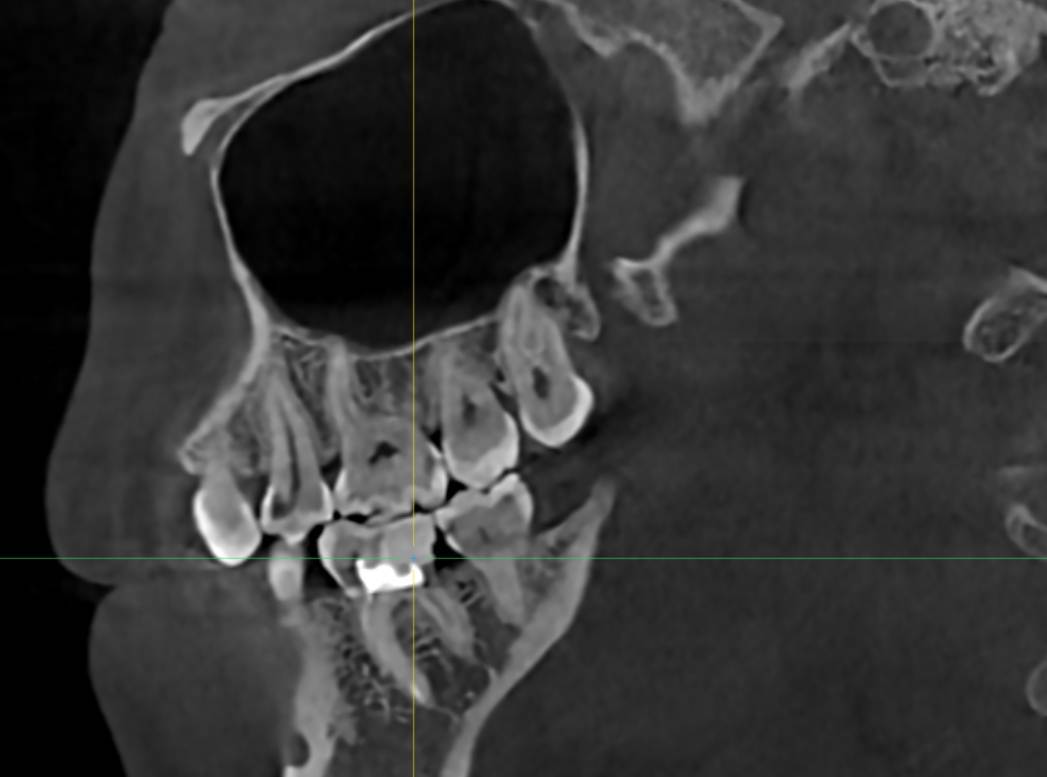

В начале января лечилт зуб в гос поликлинике, от него откололся кусочек ,врач закладывала лекарство для удаления нерва ,через 2 недели пломбировали каналы . Делали все без коффердама. Через 1,5 мес зуб стал беспокоить ,пошла сделала кт ,на кт обнаружиллсь ,что пропустили канал . Плюс сам зуб ,как по мне выглядит странно  ,как будто он очень сильно внутри распилен. Внизу зуба где начинается корень очень тонко. Консультировалась с несколькими врачами. Один сказал ,что не будем лезть в остальные каналы,они нормально пройдены ,найдём один под микроскопом и его только сделать видимо за один визит.  Пошла получить другое мнение  говорят ,что переделывать надо все ,но это все равно без гарантии ,в зубе осталось мало тканей и он треснуть может в любом случае. И все это обойдётся в крупную сумму . Вопрос что делать, можно ли пройти один канал ,чтобы не рисковать сломать зуб ,или инфекция от одного канала уже везде? На данный момент зуб реагирует на холодное и горячее ,неприятно при постукивании,покалывает .

могу прикрепить ссылку кт https://disk.picasso-diagnostic.ru/7e7c16a0-fc83-4b39-a91d-09fc2f0f5c6d/lhDs5VIbI6dIe5ZutFBMd83qtBCXS1Z7eVAnHJCdup_o_N0e2keKzT3kTDblJax1bU2DzP4M1Rvwul3J2An3UWsv.jpg.065ec6a69d86164e39dc9f22752fb54e.jpg